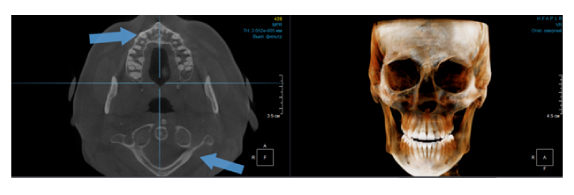

По сути воксель – это структурная единица изображения. Компьютерная томограмма состоит из вокселей, и их размер определяет качество снимка. Как правило, чем меньше FOV снимка, тем меньше и размер вокселя, а это, в свою очередь, делает изображение более качественным (рис. 3). Разные фирмы, производящие дентальные томографы пытаются конкурировать в размерах вокселя, особенно при больших зонах сканирования. Я стараюсь использовать два режима, как правило, это standart definition со средним размером вокселя и high definition с уменьшенным размером вокселя. Если намечается сложная эндодонтия, то, безусловно, high definition с минимальным значением вокселя будет крайне эффективно, но если у пациента огромное количество металла (циркон, металлокерамика и прочее) то порой именно стандартный размер вокселя помогает снизить количество артефактов и сделать изображение более читабельным.

Рис. 3. КЛКТ с зоной сканирования 5x5 см и размером вокселя 70 микрон.